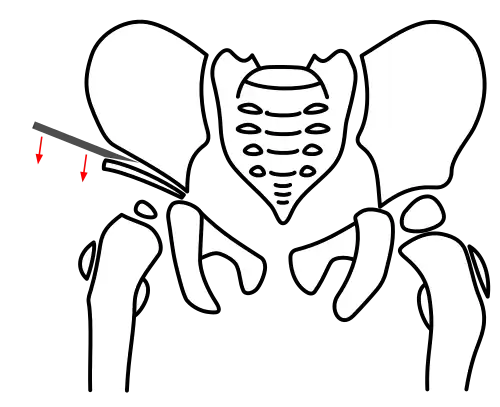

Acetabuloplasty, Step 1: Osteotomy of the ilium

Acetabuloplasty, Step 1: Osteotomy of the ilium -

All osteotomy techniques require only a small incision between the groin fold and iliac crest. The muscles are bluntly separated to expose the ilium. The periosteum is detached just above the acetabulum, and the iliac bone is laid bare.[4]

Pemberton osteotomy

In the Pemberton technique, under continuous X-ray guidance, the ilium is notched approximately 5 mm above the acetabular rim using a flat chisel, and the osteotomy is extended toward the Y-shaped physis. The acetabular fragment is then tilted downward and forward under X-ray control to achieve anatomical reconstruction.[7][10]